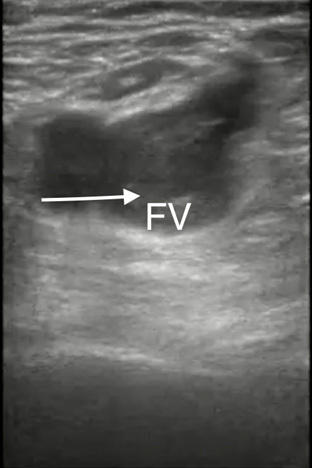

Ultrasound is the most common modality used in the ED to evaluate for DVT. Whole leg ultrasonography is performed most frequently and has a higher negative predictive value compared to proximal vein ultrasonography, but it also can detect distal thrombi for which no treatment typically is indicated.27 Not all EDs have 24-hour access to consultative ultrasonography and point-of-care ultrasound can be performed in these cases to evaluate for DVT. The two-point technique tests for compressibility of the common femoral vein and the popliteal vein, while the three-point technique also includes the superficial femoral vein.28 (See Figure 1.) A meta-analysis showed similar sensitivity, specificity, and false-negative rates between the two techniques.29

Figure 1. Femoral Vein Thrombus/Deep Vein Thrombosis |

Point-of-care ultrasound image demonstrating a femoral vein (FV) thrombus/deep vein thrombosis (white arrow) |

Image courtesy of Daniel Migliaccio, MD. |